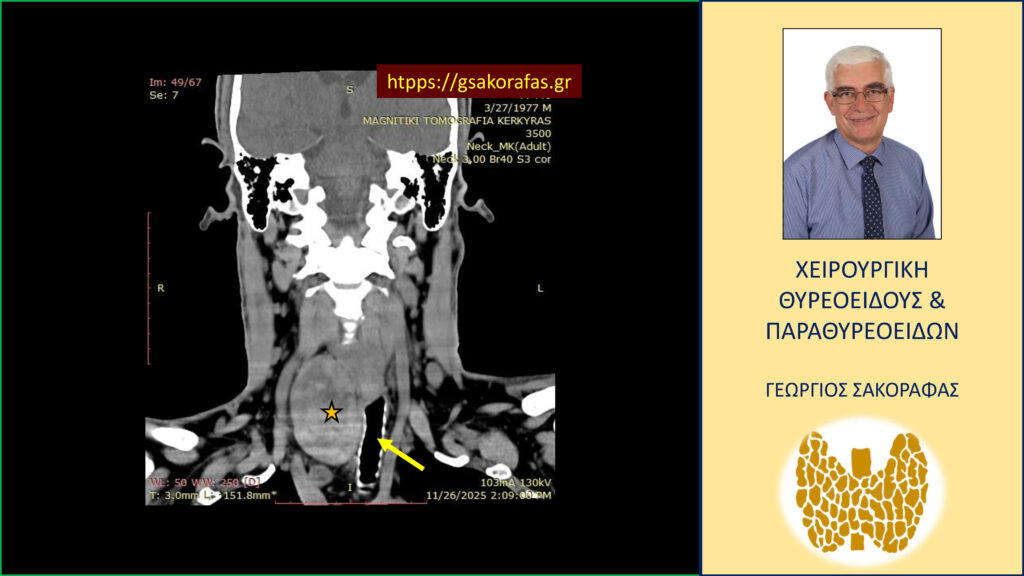

- Γιατί είμαστε σε θέση να εκτελέσουμε με ασφάλεια και αποτελεσματικότητα κάθε είδους χειρουργική επέμβαση θυρεοειδούς – παραθυρεοειδών, ακόμη και σε επιπλεγμένα (δύσκολα) περιστατικά, όπως εκτεταμένοι λεμφαδενικοί καθαρισμοί σε καρκίνο θυρεοειδούς, επεμβάσεις σε λίαν ευμεγέθεις καταδυόμενες στο μεσοθωράκιο βρογχοκήλες, υποτροπές παθήσεων θυρεοειδούς (συμπεριλαμβανομένου του καρκίνου θυρεοειδούς), υποτροπές υπερπαραθυρεοειδισμού, αδενώματα παραθυρεοειδών σε έκτοπη θέση ή λόγω υπεράριθμων παραθυρεοειδών, διάχυτη υπερπλασία παραθυρεοειδών, κλπ.